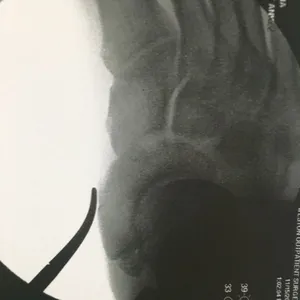

Intraop Pics Of Plantar Medial Foot Release for Chronic Exertional Compartment Syndrome in the foot